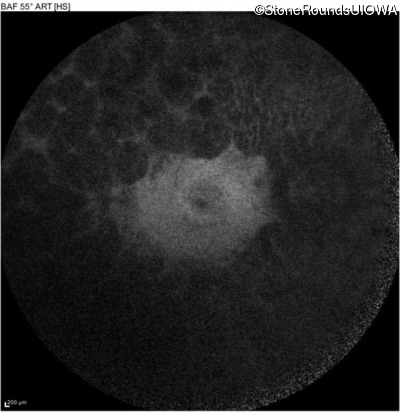

Infrared Fundus Photograph - Right - 20/50

Exemplar